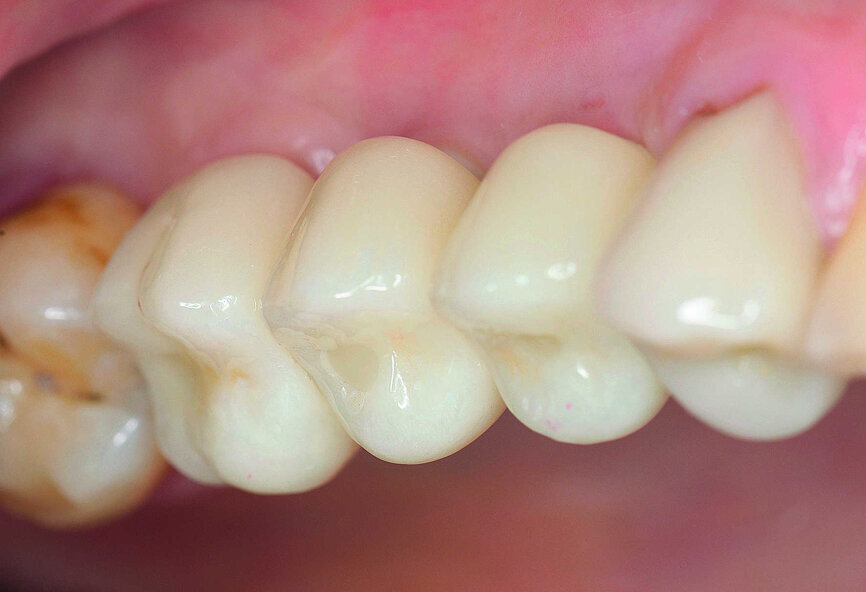

En janvier 2015, le patient, âgé de 42 ans, souhaitait une restauration globale et sans métal de sa denture, dont certaines dents manquaient ou nécessitaient un traitement (Fig. 1). Le bridge qu’il avait d’abord porté pour remplacer les dents absentes, 15 à 17, avait été retiré quelques années auparavant par le chirurgien-dentiste habituel du patient, et depuis lors l’espace n’avait jamais été restauré par une autre prothèse (Fig. 2). Le patient s’était déjà informé sur les possibilités de restauration et souhaitait le remplacement de ses dents manquantes par des implants en céramique. L’évaluation des radiographies indiquait une largeur osseuse adéquate, mais une hauteur réduite due à une résorption de l’os alvéolaire et une pneumatisation du sinus maxillaire. Une large bande de muqueuse attachée était présente dans la zone prévue pour l’émergence des implants. Selon les critères de classification du risque SAC (Simple - Avancé - Complexe) de la Société suisse d’implantologie orale, le cas était de niveau A. (Tableau 1).

Figs. 1 et 2 : Situation intra-orale initiale.